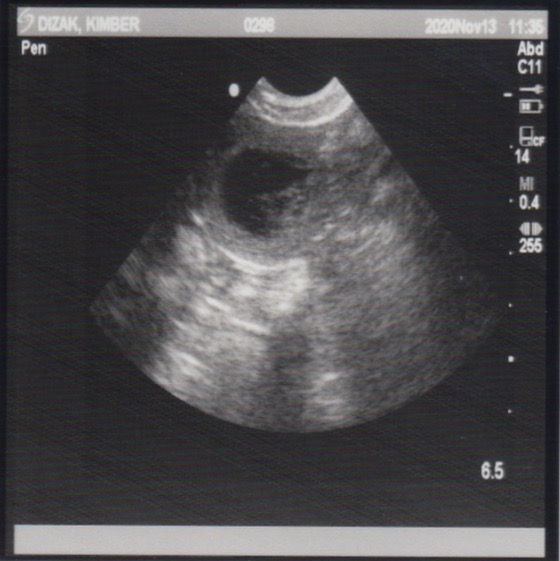

November 13, 2020 – Ultrasound

Since this was an artificial insemination and the success rate a bit lower than natural breedings, we wanted to have an ultrasound done to see if there are any little beings growing inside of Miss Kimber. Well, our repro vet confirmed this morning that Kimber is indeed pregnant!